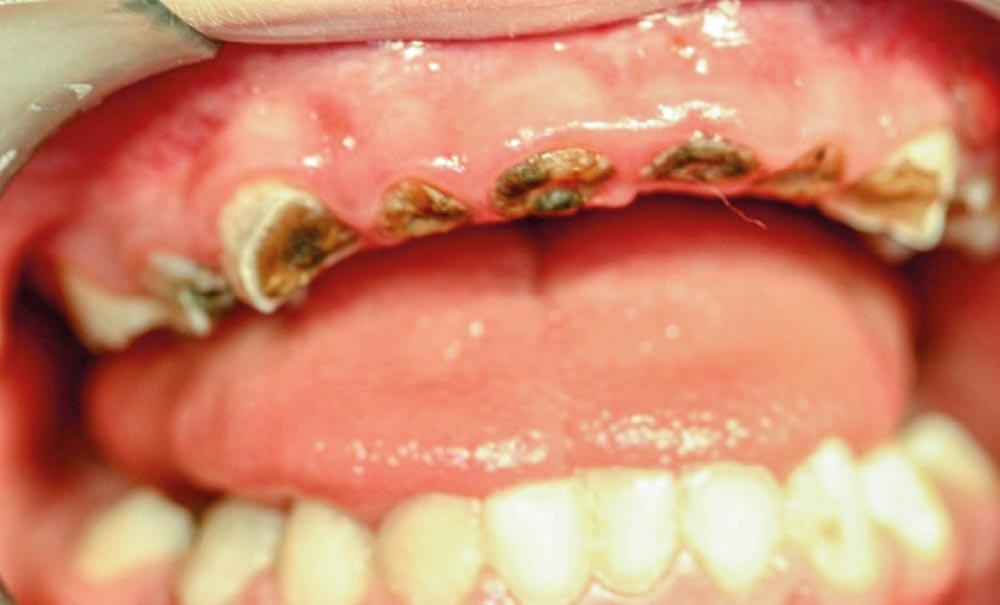

► Salomé (fig. 1) se présente avec sa maman à la consultation d’urgence pour des douleurs dentaires. Lors de l’interrogatoire, nous apprenons que la petite fille dort toutes les nuits, depuis plus de 3 ans avec un biberon (350 ml) de lait avec du sirop de grenadine. Cependant, cette alimentation nocturne semble être arrêtée depuis quelques mois à la demande du médecin qui suit Salomé. Ce praticien avait constaté de multiples caries et des foyers infectieux qui l’avaient alerté et avait demandé aux parents de consulter rapidement un chirurgien-dentiste.

► Lors des examens clinique et radiographique, nous constatons que Salomé souffre de caries précoces de la petite enfance (CPE). Pendant la consultation, nous expliquons à la maman l’importance d’une bonne hygiène alimentaire (arrêt du biberon nocturne, du grignotage…) et bucco-dentaire ainsi que de la nécessité de soins dentaires pour sa fille.

► Vu le jeune âge de cette dernière et le nombre de dents atteintes (fig. 2 et 3), nous proposons aux parents de réaliser les soins sous anesthésie générale. La maman valide cette thérapeutique. Un rendez-vous chez l’anesthésiste et une date pour l’intervention sont programmés.